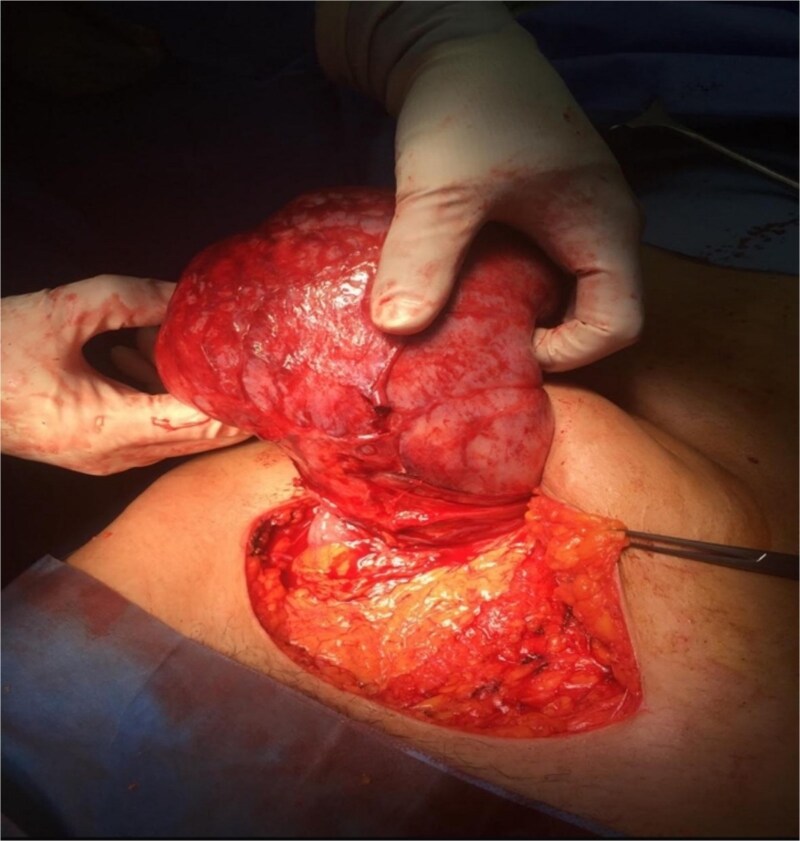

Large extraluminal gastrointestinal stromal tumours (GISTs) are rare, with varied presentations and patient profiles. This report discusses the case of a 22-year-old female presenting with a 4-month history of lower abdominal pain, weight loss, and recurrent urinary tract infections. Imaging revealed a large intra-abdominal mass (9.3 × 15.3 × 18.9 cm) originating from the stomach, extending into the pelvis, and compressing adjacent structures. During surgery, the mass was found to arise from the lesser curvature of the stomach and adhered to the transverse colon, with non-adherent extension into the pelvis and compression of adjacent organs. A gastric wedge resection and transverse colectomy were performed with aim of achieving a R0 resection. Histopathological analysis confirmed a GIST and positive resection margins. A plan for adjuvant imatinib was initiated in accordance with the European Society for Medical Oncology (ESMO) guidelines. This article details the challenges faced in the management of such a rare presentation and highlights similar reports.